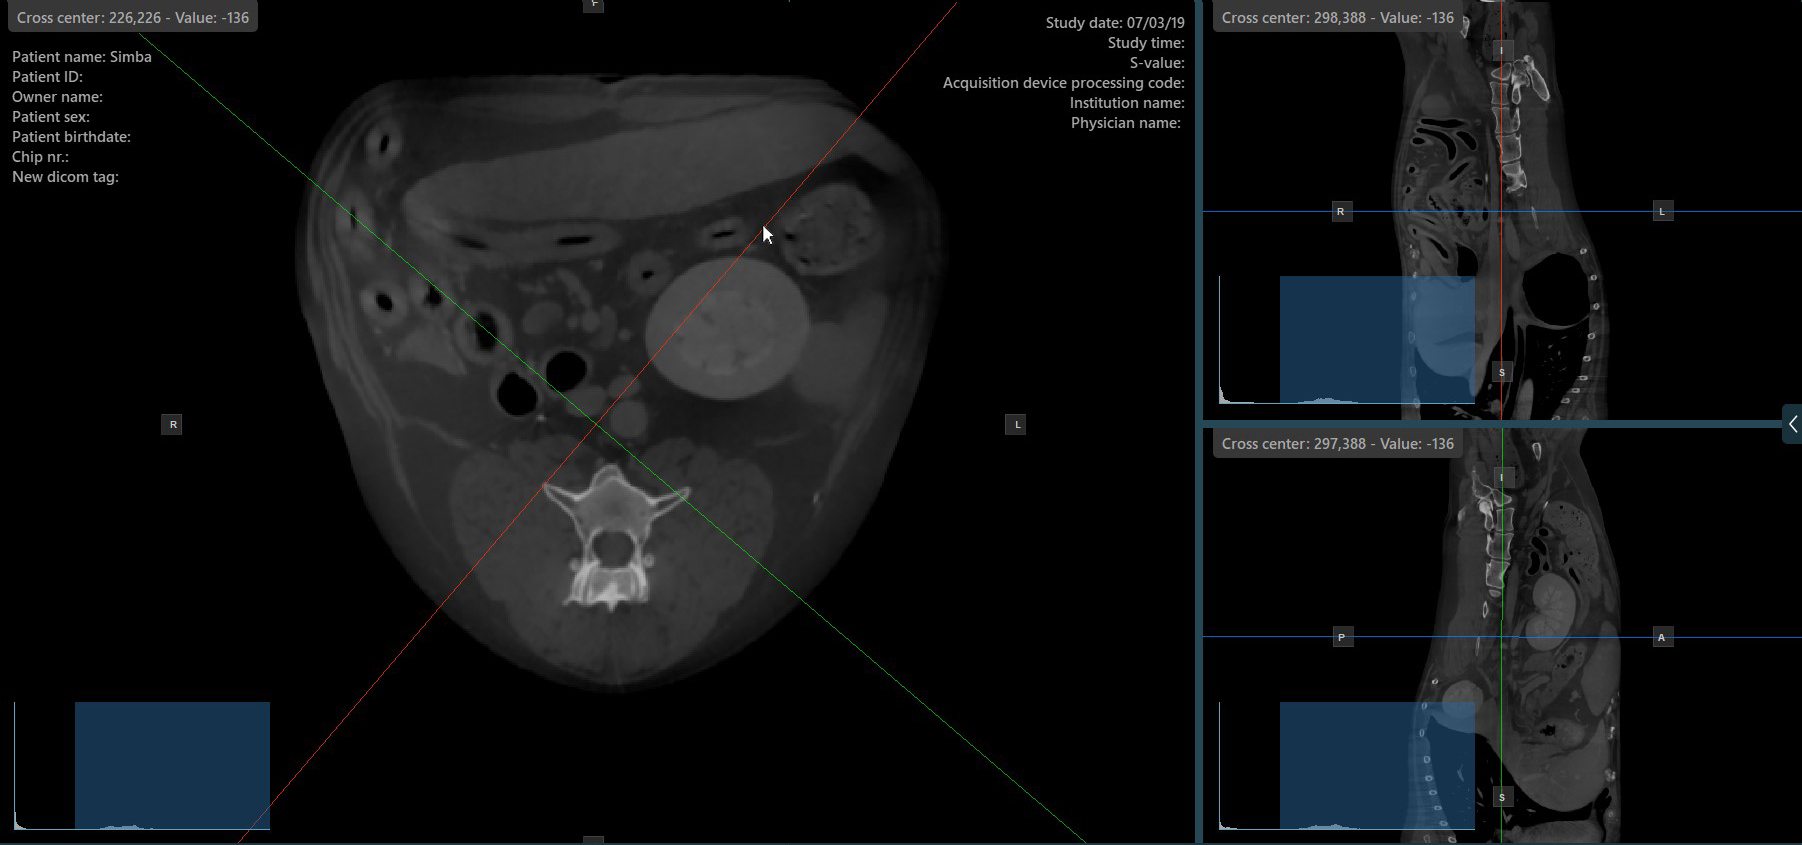

Jeder Slicer ist durch seine spezifische Farbe gekennzeichnet, die die jeweilige Bildebene darstellt:

Der blaue Slicer markiert die axiale Ebene des Objekts (senkrecht zum Boden).

Der rote Slicer markiert die koronale Ebene (parallel zum Boden).

Der grüne Slicer markiert die sagittale Ebene (senkrecht zum Körper).